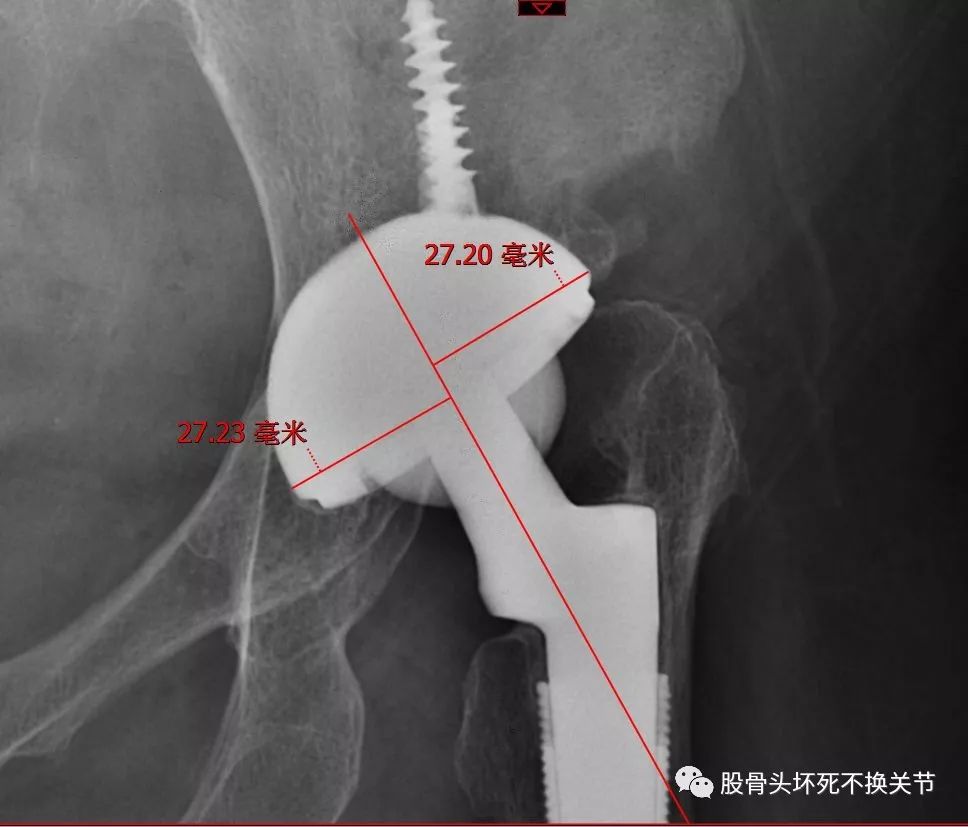

52岁,陶瓷对聚乙烯双侧置换

陶-聚乙烯关节术后8年,未见明显磨损